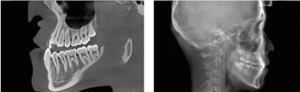

High-Resolution Dental CBCT Imaging

The system achieves image resolutions up to 2.0 lp/mm with a voxel size range of 0.05 – 0.25 mm.

Its 0.5 mm small focus tube guarantees smooth, stable, and reliable scans.

Furthermore, the high-definition image output ensures accurate diagnosis and confident treatment planning.

0.5mm small focus tube ensures outstanding image quality.

Resolution up to 2.0lp/mm, voxel size of 0.25~0.05 mm optional.

Furthermore, Panoramic Images are Reconstructed from 3D Dental CBCT data for clearer visualization

Furthermore, AI+PAN Dental CBCT Imaging enhances precision.

- The system rebuilds panoramic views directly from CBCT data using AI.

- Panoramic auto-focus and multi-layer technology select the best curve automatically.

- Therefore, the final image is cleaner and easier to read.